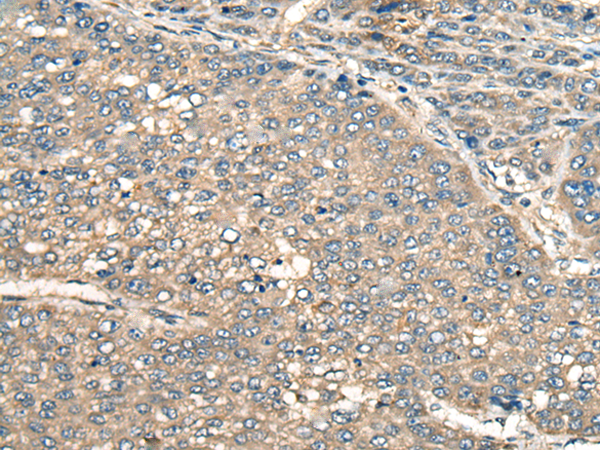

IHC (Immunohistochemistry)

(Immunohistochemistry of paraffin-embedded Human liver cancer tissue using PIAS3 Polyclonal Antibody at dilution of 1:55(×200))